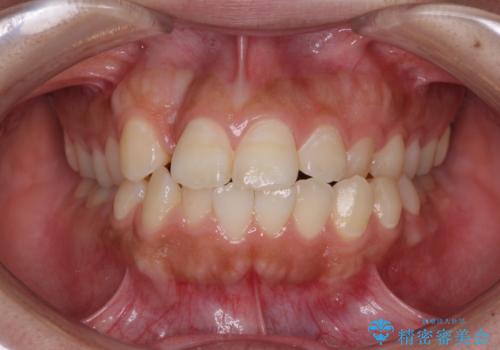

- 口元の突出感を気にして来院された患者様です。

デコボコと口元の突出感が認められたため、上下左右の第1小臼歯4本を抜歯してのワイヤー矯正を行うこととしました。

上顎歯列の横幅が狭く、下顎大臼歯の歯軸が舌側に倒れていたため、急速拡大装置により上顎骨を側方に拡大し、咬み合わせを改善することとしました。